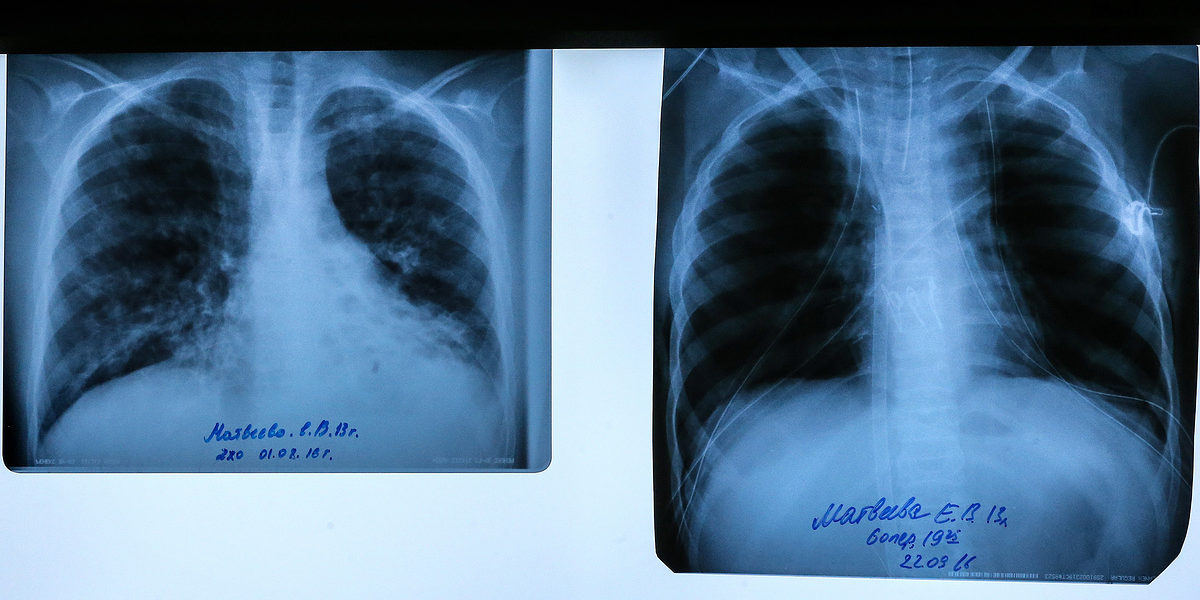

В минздраве пояснили, что при муковисцидозе нарушается работа поджелудочной железы и легких. Всего в России насчитывается более 3 тыс. человек, страдающих этим заболеванием, оно — одно из самых распространенных наследственных болезней. В Подмосковье свыше 170 детей болеют муковисцидозом.